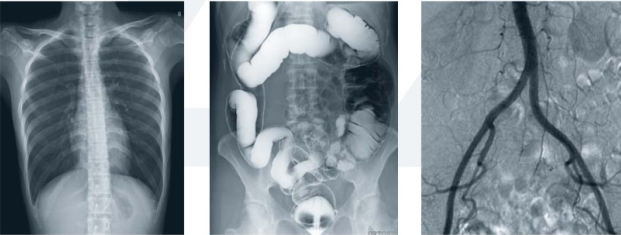

胃腸造影離不開(kāi)現(xiàn)代化的數(shù)字化胃腸顯影方式(一類(lèi)運(yùn)用常規(guī)胃腸機(jī)達(dá)到檢查目的;另一類(lèi)則運(yùn)用新推出的動(dòng)態(tài)DR達(dá)到檢查目的),它是一種能通過(guò)造影診斷用來(lái)檢查胃腸道疾病的X線(xiàn)檢查設(shè)備,是檢查各種潰瘍、腫瘤及異物等疾病的主要檢查方法之一。

動(dòng)態(tài)DR胃腸造影檢查和消化內(nèi)鏡相輔相成,在胃腸道疾病的診斷方面具有其他檢查方法無(wú)可比擬的優(yōu)勢(shì)。僅在考慮特異性、適用性、普遍性的胃腸檢查上不難發(fā)現(xiàn),動(dòng)態(tài)DR胃腸造影檢查略有優(yōu)勢(shì)。特別是疑難病例上,全面分析胃腸大概狀況,離不開(kāi)造影的有效應(yīng)用。

同時(shí), 動(dòng)態(tài)DR的應(yīng)用實(shí)現(xiàn)了狀態(tài)和功能同時(shí)記錄觀(guān)察,既可留下大量的資料,又拓寬了檢查范圍,對(duì)臨床工作者的使用慣性和操作都有不可替代的地位。